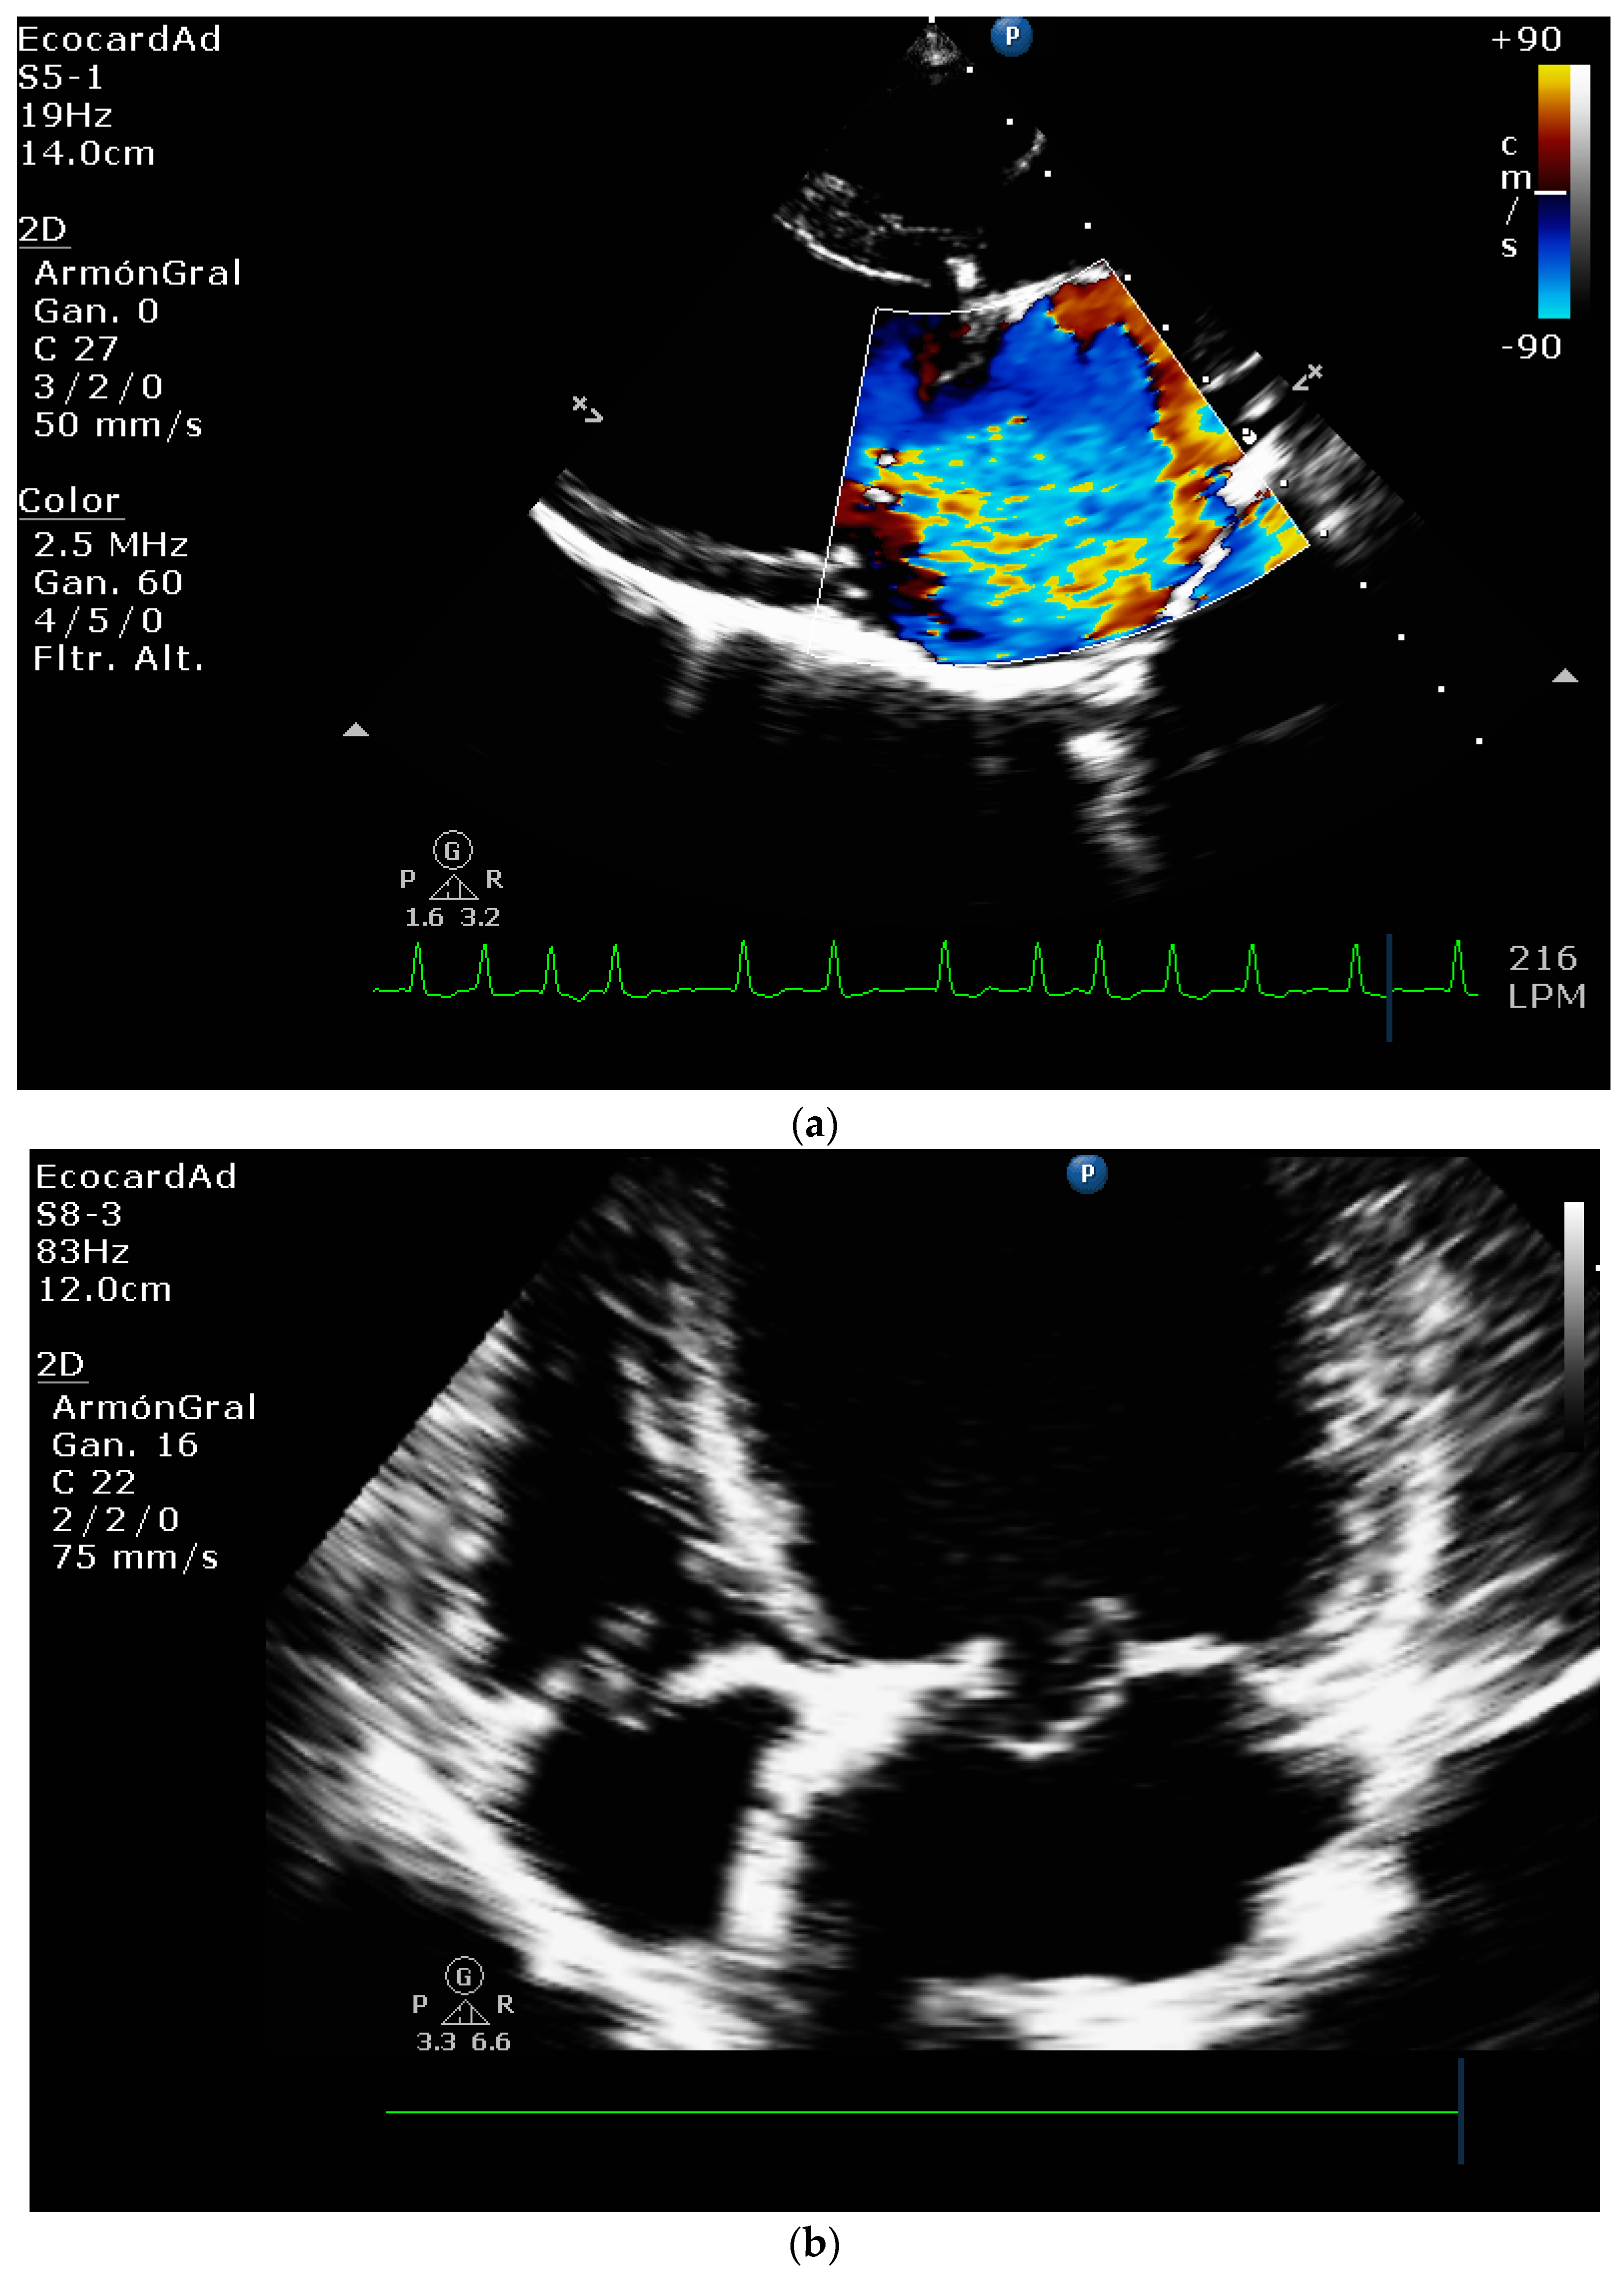

4.8.1. Evaluation of the Regurgitant Area

4.8.2. Presence of Vena Contracta

| Color flow imaging of the mitral regurgitation jet area | The most commonly used technique for assessing severity in dogs. The former method is not used in humans as it is not considered reliable for determining the severity of mitral insufficiency. |